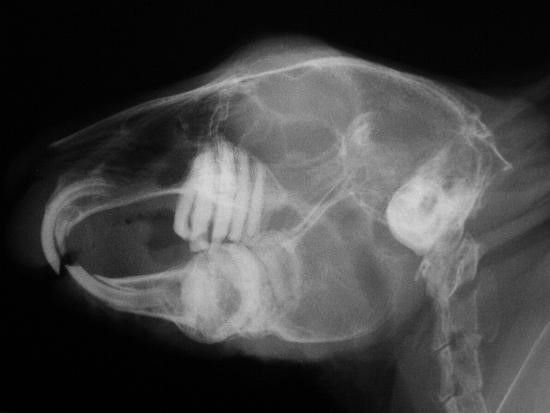

Знімок щелепи кролика

У кроликів, як і у людини, можуть захворіти зуби. Причиною є карієс, випадково зламаний корінь зуба, пульпіт. У гризунів передні різці мають властивість сточуватися, а тому ростуть постійно, все життя. Занадто подовжені різці починають заважати жувати, чіпляються за щоки, болять. Така патологія називається малокклюзіей і сприяє формуванню неправильного прикусу. Проблема вирішується шляхом механічного підпилювання зубів.

Малокклюзія у кролика